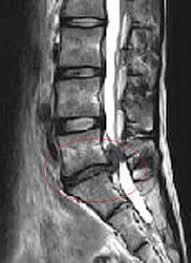

レントゲンやMRIで異常が見つからない腰痛が8割ということは、2割の原因が特定できる腰痛は、原因となる場所だけを治せば腰痛は治るのかと言えばそうとは限りません。

当院に来院される方にも、腰椎の椎間板を全部取り除いたにも関わらず腰痛やヘルニア症状いわゆる下肢の痺れや痛みを伴う方はかなりいらっしゃいます。

椎間板が飛び出ているのが原因であれば、それを解消すれば腰痛も解消されるはず。

ですが、手術によって飛び出ている椎間板を取り除いても解消されないということは、結局椎間板が飛び出ていることも原因ではなく結果だったのではないでしょうか?

結局は画像上の異常と症状には何ら関連はないと言わざるを得ない状態なのです。